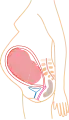

La grossesse, appelée aussi gestation humaine, est l'état d'une femme enceinte, c'est-à-dire portant un embryon ou un fœtus humain, en principe au sein de l'utérus, qui est dit gravide. En général, elle fait suite à un rapport sexuel, débute selon le point de vue à partir de la fécondation (fusion d'un ovule et d'un spermatozoïde) ou de la nidation (implantation de l'embryon dans l'utérus), et se déroule jusqu'à l'expulsion de l'organisme engendré. La durée moyenne de la fécondation à l'accouchement pour une grossesse unique est de 38 semaines et deux jours[1], soit un peu moins de neuf mois, une durée largement reprise dans la culture. Dans les faits, cette durée est variable selon les personnes et le déroulement de la grossesse. Ainsi, une grossesse normale dure entre 37 et 41 semaines d'aménorrhée (SA) ; on parlera alors de grossesse menée à terme. Pour une durée inférieure à 37 SA, on parle de prématurité et, pour une durée supérieure à 41 SA, on parle de postmaturité.

La grossesse s'accompagne de modifications importantes de l'organisme, que ce soit sur le plan physique, notamment au niveau de l'utérus, ou sur le plan psychique. Plusieurs pathologies peuvent survenir au cours de la grossesse, qu'elles soient spécifiques ou non. Certaines de ces pathologies, parfois sans conséquence en dehors de la grossesse, peuvent avoir un retentissement important sur l'embryon ou le fœtus. En conséquence, une adaptation du mode de vie et un suivi particulier sont conseillés pour la femme enceinte. La spécialité médicale concernée est l'obstétrique. La grossesse peut aussi avoir des conséquences culturelles, sociales ou économiques pour les parentes et parents, notamment dans le cas des grossesses à l'adolescence ou de grossesses non désirées.

Modifications physiques de l'organisme maternel